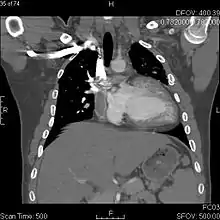

The Fontan procedure or Fontan–Kreutzer procedure is a palliative surgical procedure used in children with univentricular hearts. It involves diverting the venous blood from the inferior vena cava (IVC) and superior vena cava (SVC) to the pulmonary arteries without passing through the morphologic right ventricle; i.e., the systemic and pulmonary circulations are placed in series with the functional single ventricle. The procedure was initially performed in 1968 by Francis Fontan and Eugene Baudet from Bordeaux, France, published in 1971, simultaneously described in 1971 by Guillermo Kreutzer from Buenos Aires, Argentina, and finally published in 1973.

The Fontan procedure is used in pediatric patients who possess only a single functional ventricle, either due to lack of a heart valve (e.g. tricuspid or mitral atresia), an abnormality of the pumping ability of the heart (e.g. hypoplastic left heart syndrome or hypoplastic right heart syndrome), or a complex congenital heart disease where a bi-ventricular repair is impossible or inadvisable. The single ventricle is doing nearly twice the expected amount of work because it has to pump blood for the body and lungs. Patients typically present as neonates with cyanosis or congestive heart failure.[1] Fontan completion is usually carried out when the patient is 2–5 years of age, but is also performed before 2 years of age.[2][3]

The first stage, also called a Bidirectional Glenn procedure or Hemi-Fontan (see also Kawashima procedure), involves redirecting oxygen-poor blood from the top of the body to the lungs. That is, the pulmonary arteries are disconnected from their existing blood supply (e.g. a shunt created during a Norwood procedure, a patent ductus arteriosus, etc.). The superior vena cava (SVC), which carries blood returning from the upper body, is disconnected from the heart and instead redirected into the pulmonary arteries. The inferior vena cava (IVC), which carries blood returning from the lower body, continues to connect to the heart.

The second stage, also called Fontan Kreutzer completion, involves redirecting the blood from the IVC to the lungs. At this point, the oxygen-poor blood from upper and lower body flows through the lungs without being pumped (driven only by the pressure that builds up in the veins). This corrects the hypoxia and leaves the single ventricle responsible only for supplying blood to the body.